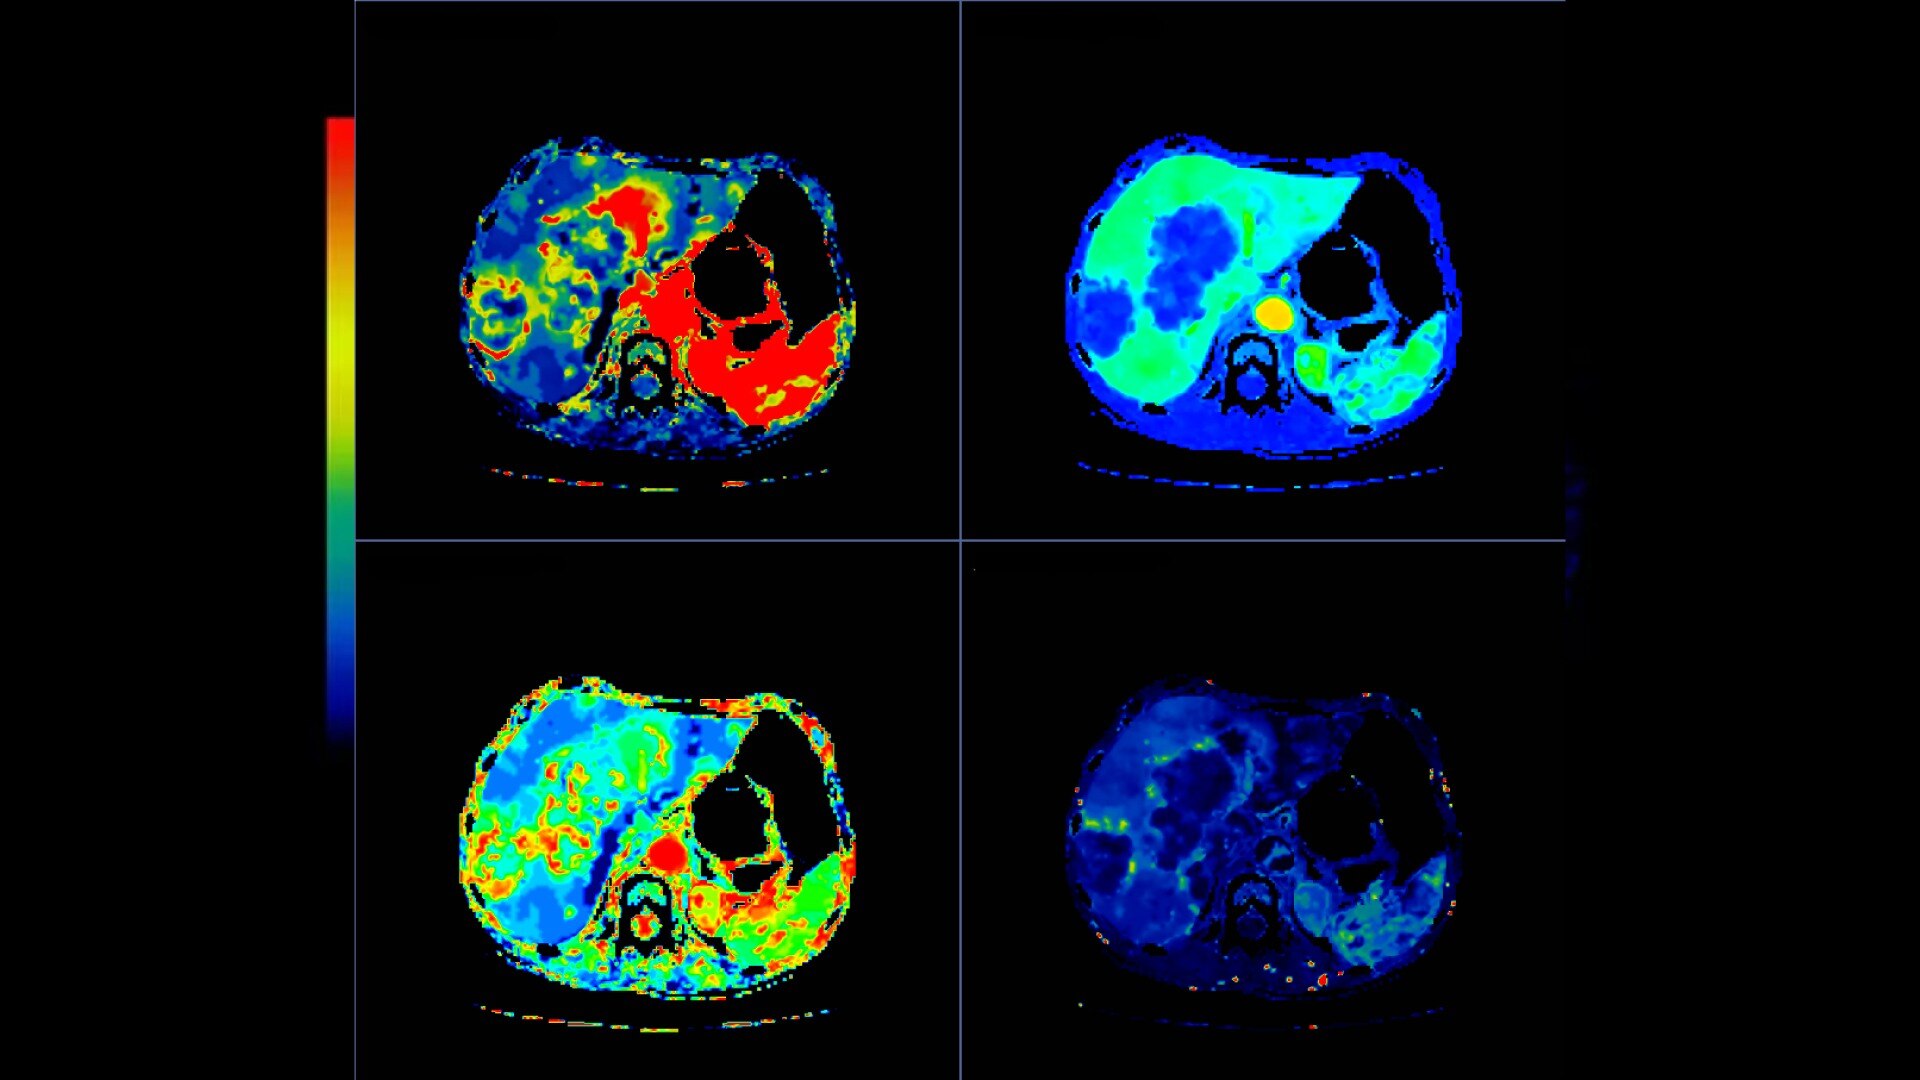

CT Body Tumor Protocol

• Automatically produces functional maps once the user selects an artery using a simple and intuitive workflow

• Leverages most of the advanced algorithm settings that are part of the Brain Stroke protocol

• Optimized protocols for pancreas, prostate, kidney, soft tissue, spleen, bone and liver perfusion

• CT Non-Rigid Registration: Fully automated protocols used for dynamic body acquisitions to register data for use in perfusion analysis